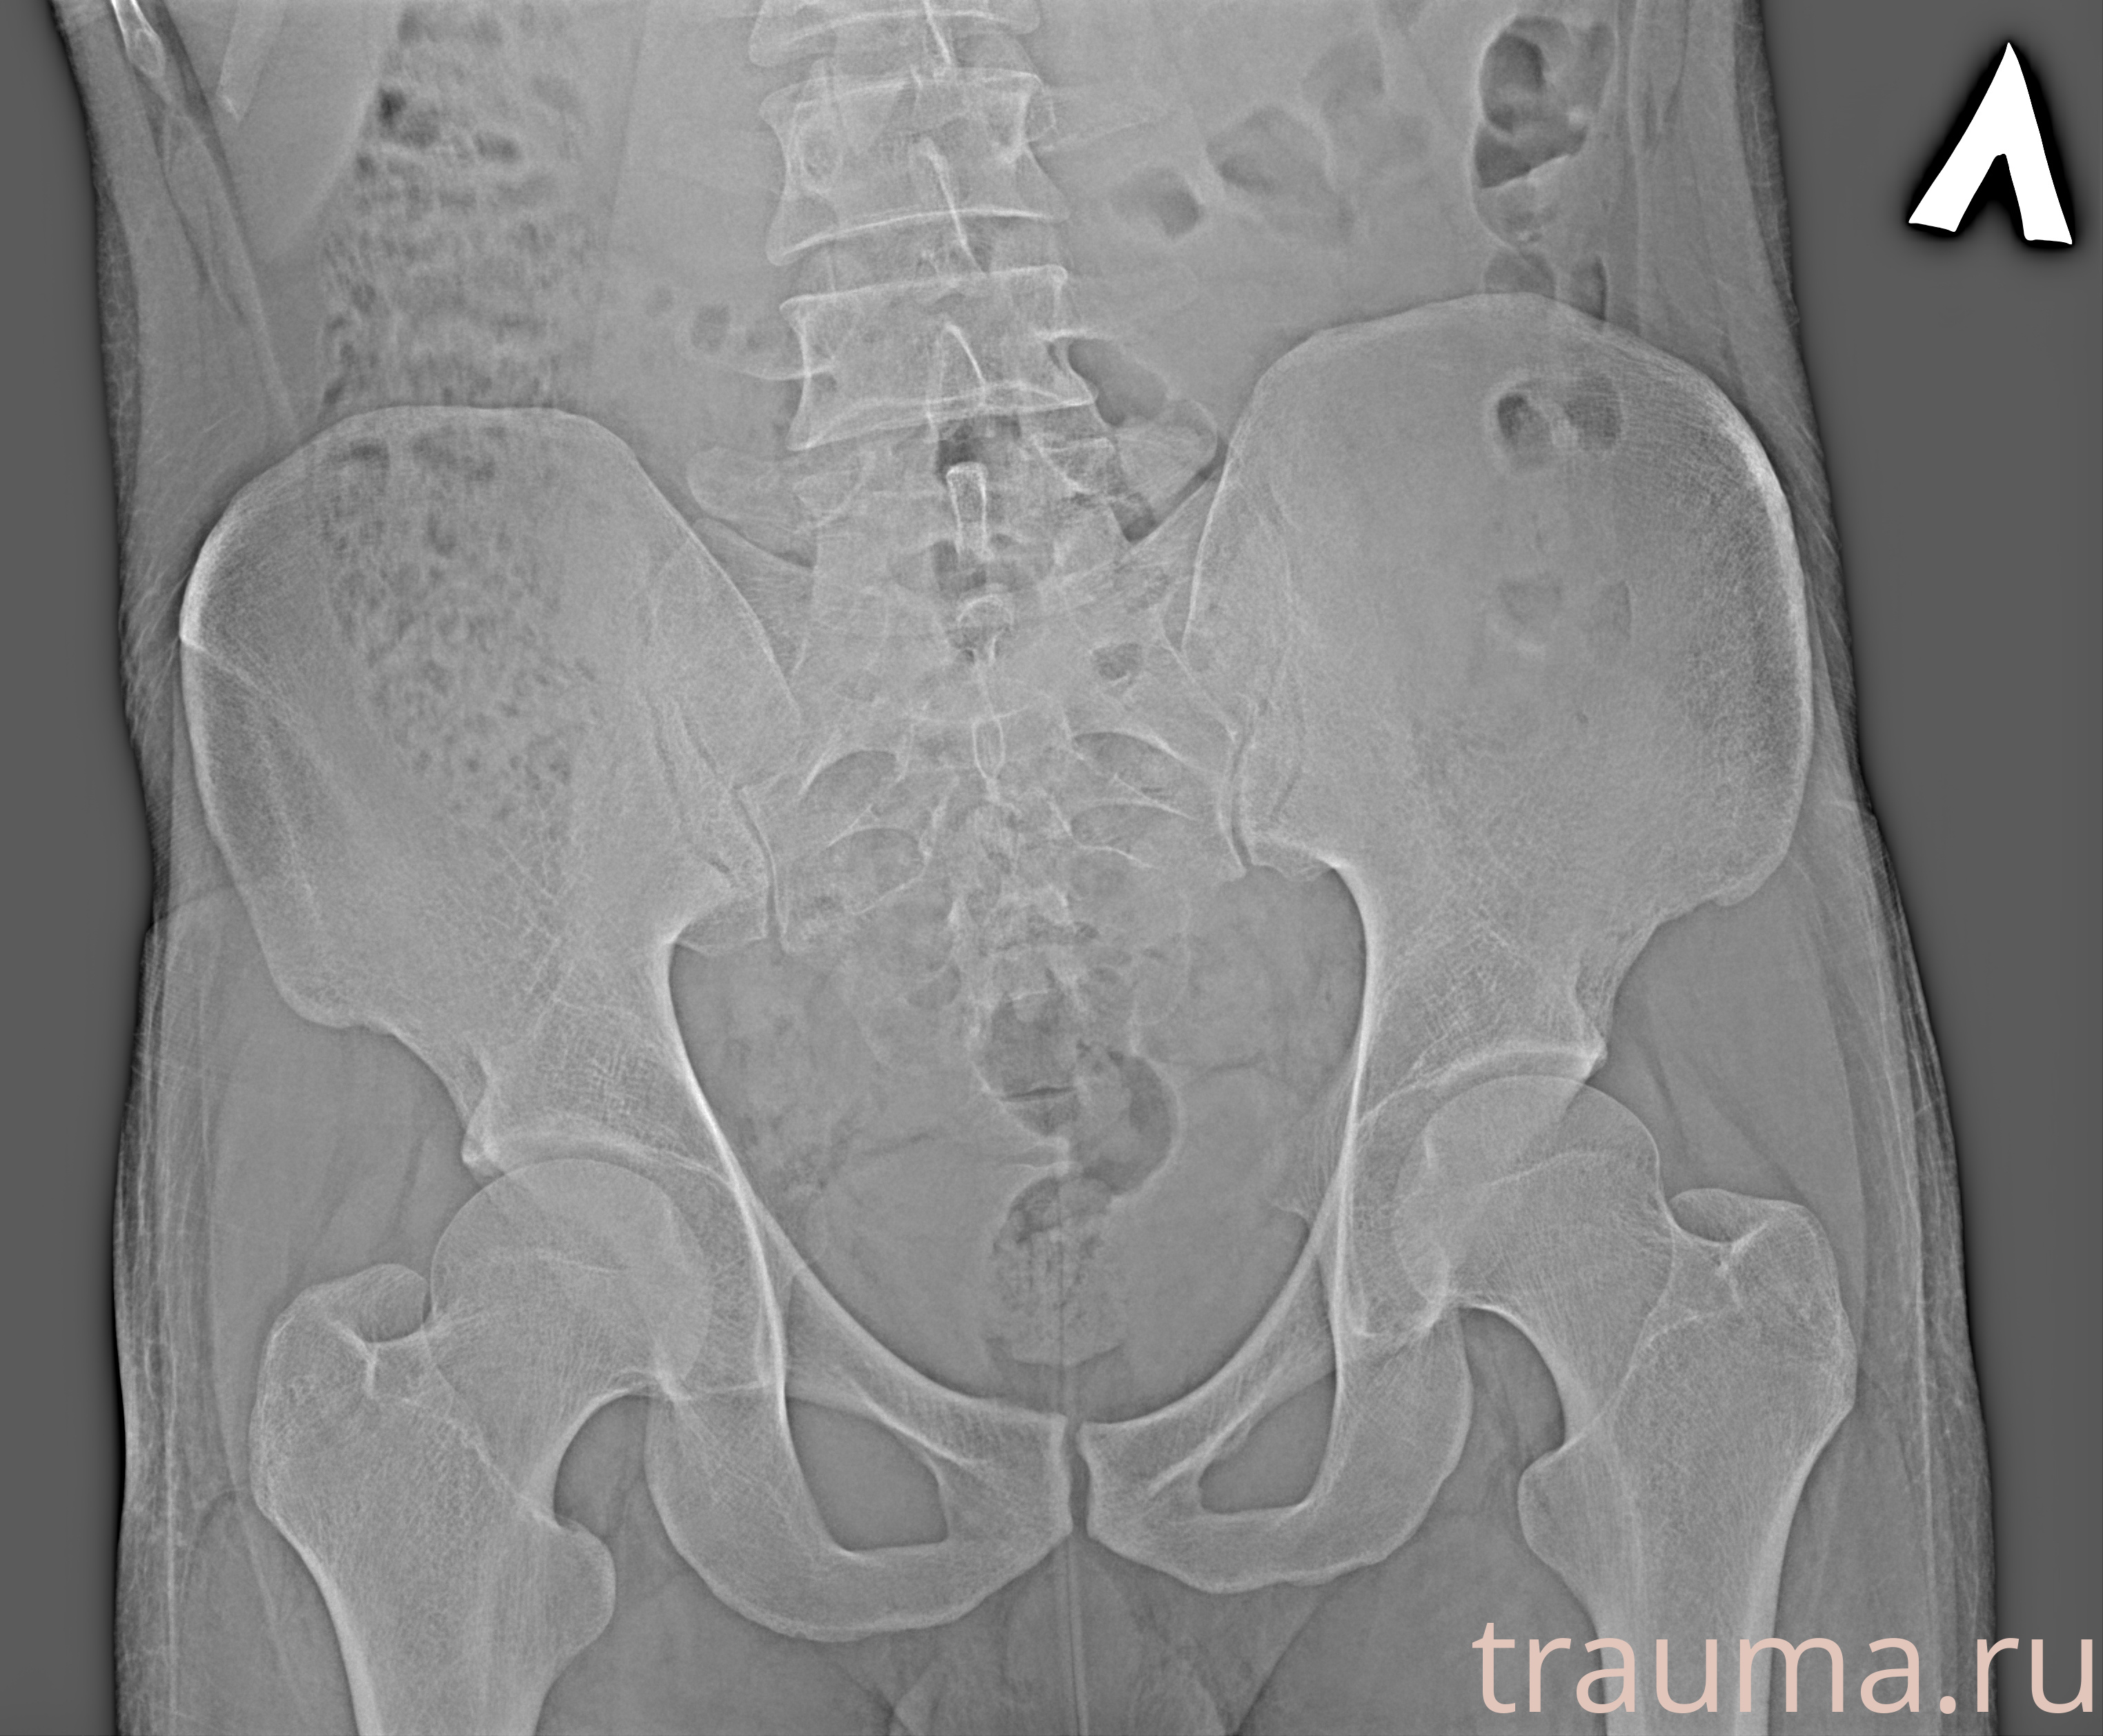

Рентгенограммы

Рентген на дому: по вашему адресу приезжает врач-рентгенолог, травматолог-ортопед с мобильным рентгеновским аппаратом, проводит диагностику травмы или заболевания, делает необходимые рентгенограммы, дает рекомендации по дальнейшему лечению. Получить качественные снимки в домашних условиях возможно благодаря уникальной методике, разработанной МосРентген Центром для института  Склифосовского